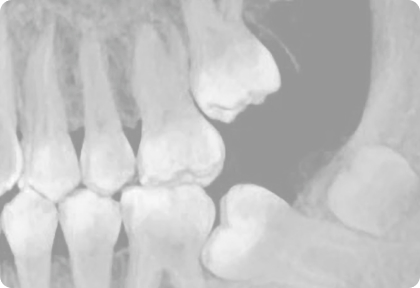

Остеопатия глазами ортодонта. Пост №3 – когда пациенту нужно обратиться к остеопату?

Если в процессе нашего лечения предполагается изменение положения нижней челюсти, например, при дистальном прикусе у растущего пациента или вынужденном положении челюсти со смещением вбок, то это, безусловно, приведет к изменению мышечного баланса во всем теле.

Здесь хочется, чтобы кто-то из профессионалов (остеопат, ортопед) контролировал процесс и взял на себя ответственность за пациента. В таком случае я прошу показаться до начала нашего лечения, а далее следовать рекомендациям специалиста.  Мы, как ортодонты, можем прислушаться к советам коллег и, например, активировать твин-блок ребенку не одномоментно, а постепенно.